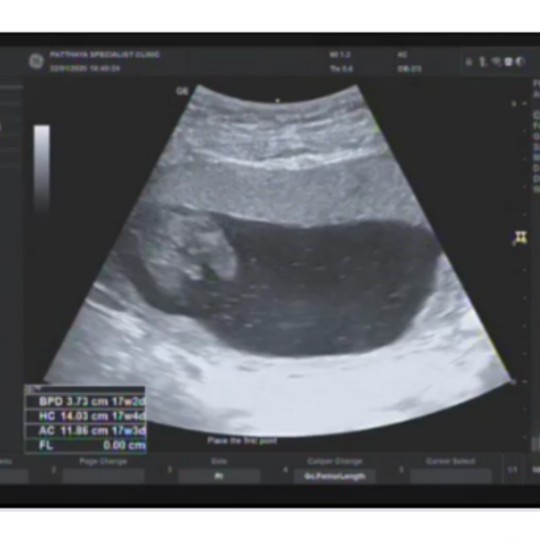

เห็นน้องชัดมากค่ะตอนซาว13สัปดาห์เองค่ะอยากรู้ว่าจะทราบเพศไหมค่ะ

13สัปดาห์

ชายค่ะ